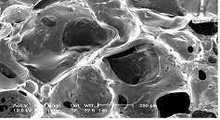

도 2는 본 발명에 따라 제조된 폴리우레탄 폼 드레싱재 접촉층 단면의 주사전자현미경 사진Figure 2 is a scanning electron micrograph of the cross section of the polyurethane foam dressing material prepared according to the present invention

도 2는 후술하는 본 발명의 실시예 1에 따라 제조된 상처면 접촉층(10)의 주사전자현미경(SEM) 사진(× 100)으로서, 이는 기존의 선행 기술 혹은 타제품의 주사전자현미경 사진과 명확히 구분된다.FIG. 2 is a scanning electron microscope (SEM) photograph (× 100) of a wound

도 3은 본 출원인의 선행 기술인 대한민국 특허 제553078호의 접촉층(흡수층과 접촉층 일체형), 도 4a,b는 미국 특허 제5,445,604호, 도 5a,b는 미국 특허 제5,064,653호의 각 흡수층(a)과 상처면 접촉층(b)의 주사전자현미경(SEM) 사진(각× 100)이다.3 is a contact layer (absorption layer and contact layer integrated) of the Republic of Korea Patent No. 553078, the prior art of the applicant, Figures 4a, b is U.S. Patent No. 5,445,604, Figures 5a, b and each absorbing layer (a) of U.S. Patent No. 5,064,653 Scanning electron microscope (SEM) photograph (angle x 100) of the wound surface contact layer (b).

도면에서 확인할 수 있는 바와 같이, 흡수층과 접촉층이 일체화된 본 발명의 상처면 접촉층(10)에서는 선행 기술에 비해서도 셀의 크기가 작고 촘촘하여 수분을 함유하는 보수율이 높을 것으로 예상되나, 미국 특허 제5,445,604호 및 제5,064,653호의 상처면 접촉층 및 흡수층은 셀의 크기가 크고, 셀 내에 포아가 많아 보수력이 떨어지며, 상처면 접촉층은 포아의 크기가 커 상처면에 달라 붙는 현상이 예상된다.As can be seen in the figure, in the wound